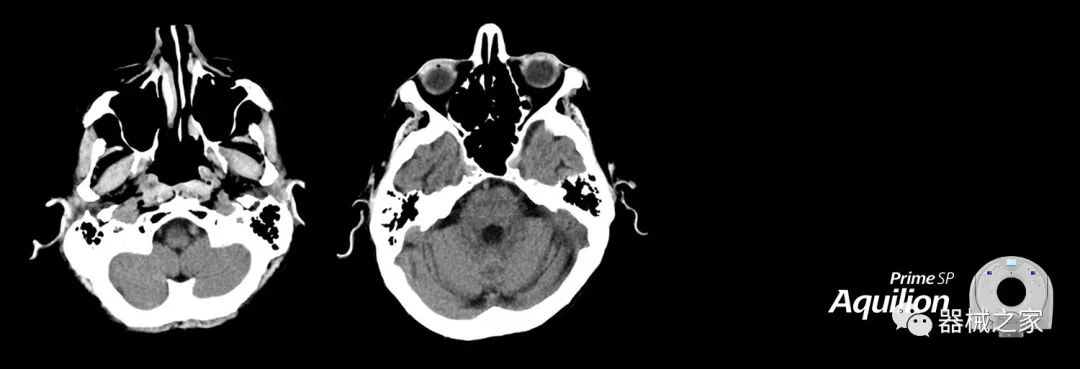

在以患者為中心的放射腫瘤學領域,計算機斷層掃描(CT)的可訪問性,可重復性和靈活性至關重要。為了建立這些價值,佳能醫(yī)療系統(tǒng)美國公司現(xiàn)在正在擴大其放射腫瘤學CT模擬產(chǎn)品,包括Aquilion Prime SP和Aquilion Lightning 80高級CT系統(tǒng)。除了Aquilion LB之外,Aquilion Prime SP和Aquilion Lightning 80現(xiàn)在還包括放射治療(RT)選項,可為腫瘤學規(guī)劃提供高質(zhì)量的CT成像和精密工具。

擴展視野(EFOV)可以看到更多的解剖結構。Aquilion LB采用85 cm EFOV,而Aquilion Prime SP和Aquilion Lightning 70采用70 cm EFOV。

Aquilion Prime SP使設施能夠處理具有挑戰(zhàn)性的案例,同時為員工提供快速,靈活和高效的解決方案。

兩個CT系統(tǒng)均采用0.5 mm x 80排PUREViSION探測器技術(可配置并從80-160現(xiàn)場升級),78 cm孔徑,50 cm視野,AIDR(自適應迭代劑量減少)3-D和SEMAR(單個)能量金屬神器減少)技術。

Aquilion LB專為滿足腫瘤學挑戰(zhàn)而設計,同時優(yōu)先考慮患者護理。Aquilion LB的內(nèi)徑為90 cm,能夠幫助復雜的患者設置并提高患者的舒適度。CT模擬定位可以輕松鏡像放射治療定位,更加自信。該系統(tǒng)采用0.5 mm x 16排(32層)PUREViSION探測器技術,70 cm視野,AIDR 3D和SEMAR技術。